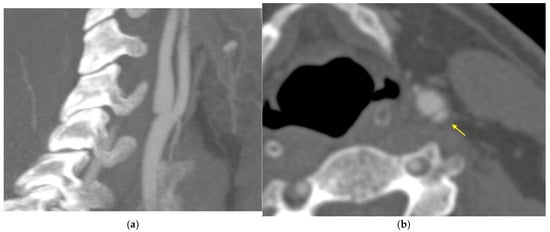

2. Case History